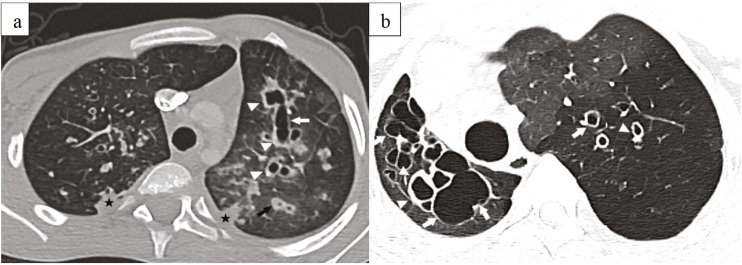

Methods: Children aged 0-18 years with a CT-confirmed diagnosis of BE were enrolled. Data on demographics, clinical characteristics, and imaging results were collected retrospectively from medical records. The Bhalla score was used to assess BE severity. Patients were categorized into CF-related and non-CF BE groups. The two groups were compared with respect to clinical features, growth z-scores, hospitalization frequency, and pulmonary function test outcomes.

Results: A total of 157 patients were analyzed. Among them, CF accounted for 23.6% of cases, and while the leading causes in the non-CF group were post-infectious BE (28%), immunodeficiency (19.8%), and primary ciliary dyskinesia (12.8%). The CF group presented at an earlier age, had a longer follow-up period, and experienced more frequent hospitalizations (p < 0.001). In the CF group, weight, height, and body mass index z-scores significantly improved from the initial to the final assessment (p = 0.010, p = 0.006, and p = 0.026, respectively), whereas no such improvement was observed in the non-CF group. Severe Bhalla scores were more frequently observed in the CF group (p < 0.001). Among CF patients, Bhalla scores showed a strong correlation with forced expiratory volume in one second (FEV1) in univariate analysis (r = 0.846, p < 0.001), though this was not significant in multivariable analysis (p = 0.434). In the non-CF group, there was no correlation between Bhalla scores and final FEV1 values (p = 0.148, r = 0.212).

Conclusion: The results underscore distinct clinical trajectories between CF and non-CF BE in children. Improvements in CF patients suggest the effectiveness of structured clinical management, whereas inconsistent outcomes in non-CF patients point to the need for standardized follow-up protocols. While the Bhalla score may indicate the extent of structural lung disease in CF, it does not independently predict lung function, and therefore should be used as a supplementary, not solitary, measure of disease severity.